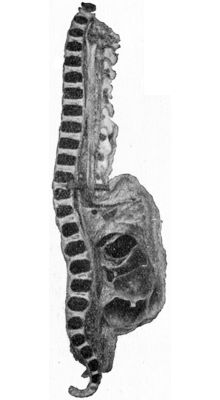

| 212. | Radiogram of Museum Specimen of Pott's Disease in a Child | 435 |